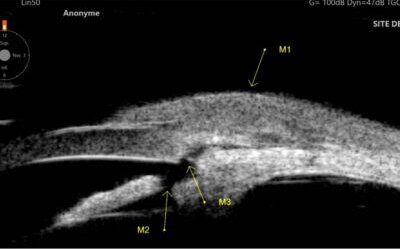

La présence d’un AIC étroit est très fréquente dans la population générale contrairement aux crises aigües de fermeture de l’angle qui sont beaucoup plus rares. L’examen gonioscopique (statique et dynamique) reste l’examen de référence de l’analyse de l’angle...